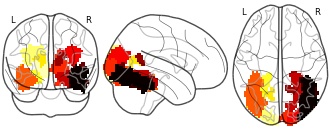

"name": "Multi_VBMsmaller_fMRIenhanced",

"description": "Multi-modal analysis in BPD. Brain regions exhibiting smaller gray matter and enhanced activation during emotion processing in BPD compared to healthy controls. Note: Results were thresholded at p<.0025. Note2: Results were updated (see Erratum for this publication).",

"name": "Multi_VBMsmaller_fMRIdecreased",

"description": "Multi-modal analysis in BPD. Brain regions exhibiting smaller gray matter and decreased activation during emotion processing in BPD compared to healthy controls. Note: Results were thresholded at p<.0025. Note2: Results were updated (see Erratum for this publication).",